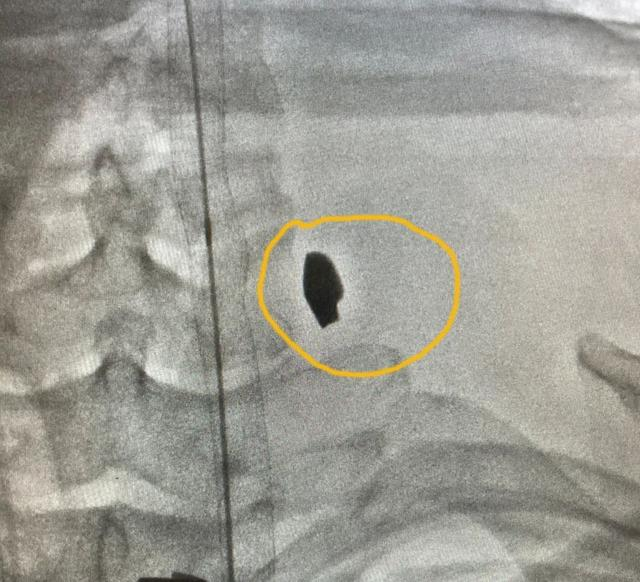

在DSA(数字减影血管造影)检查下,一颗直径约8毫米的异物在影像中显露高密度白色身形,刚好卡在颈椎间隙,没有伤到颈椎。医生们松了一口气,这也意味着,一切都在他们的掌握中。

卡在颈椎间隙的异物